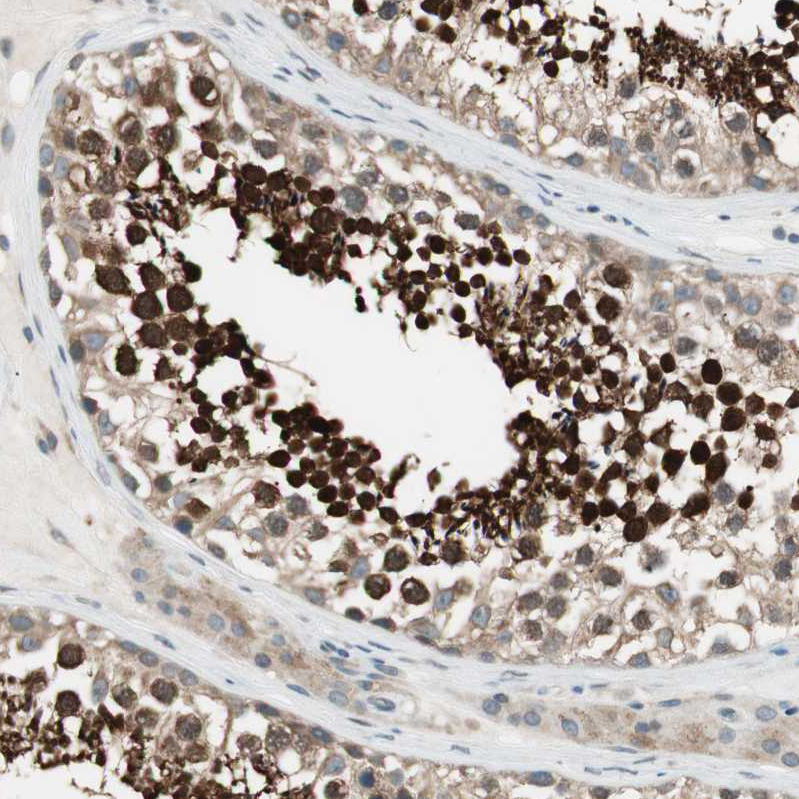

Immunohistochemical staining of human testis shows strong nuclear and cytoplasmic positivity in cells in seminiferous ducts.